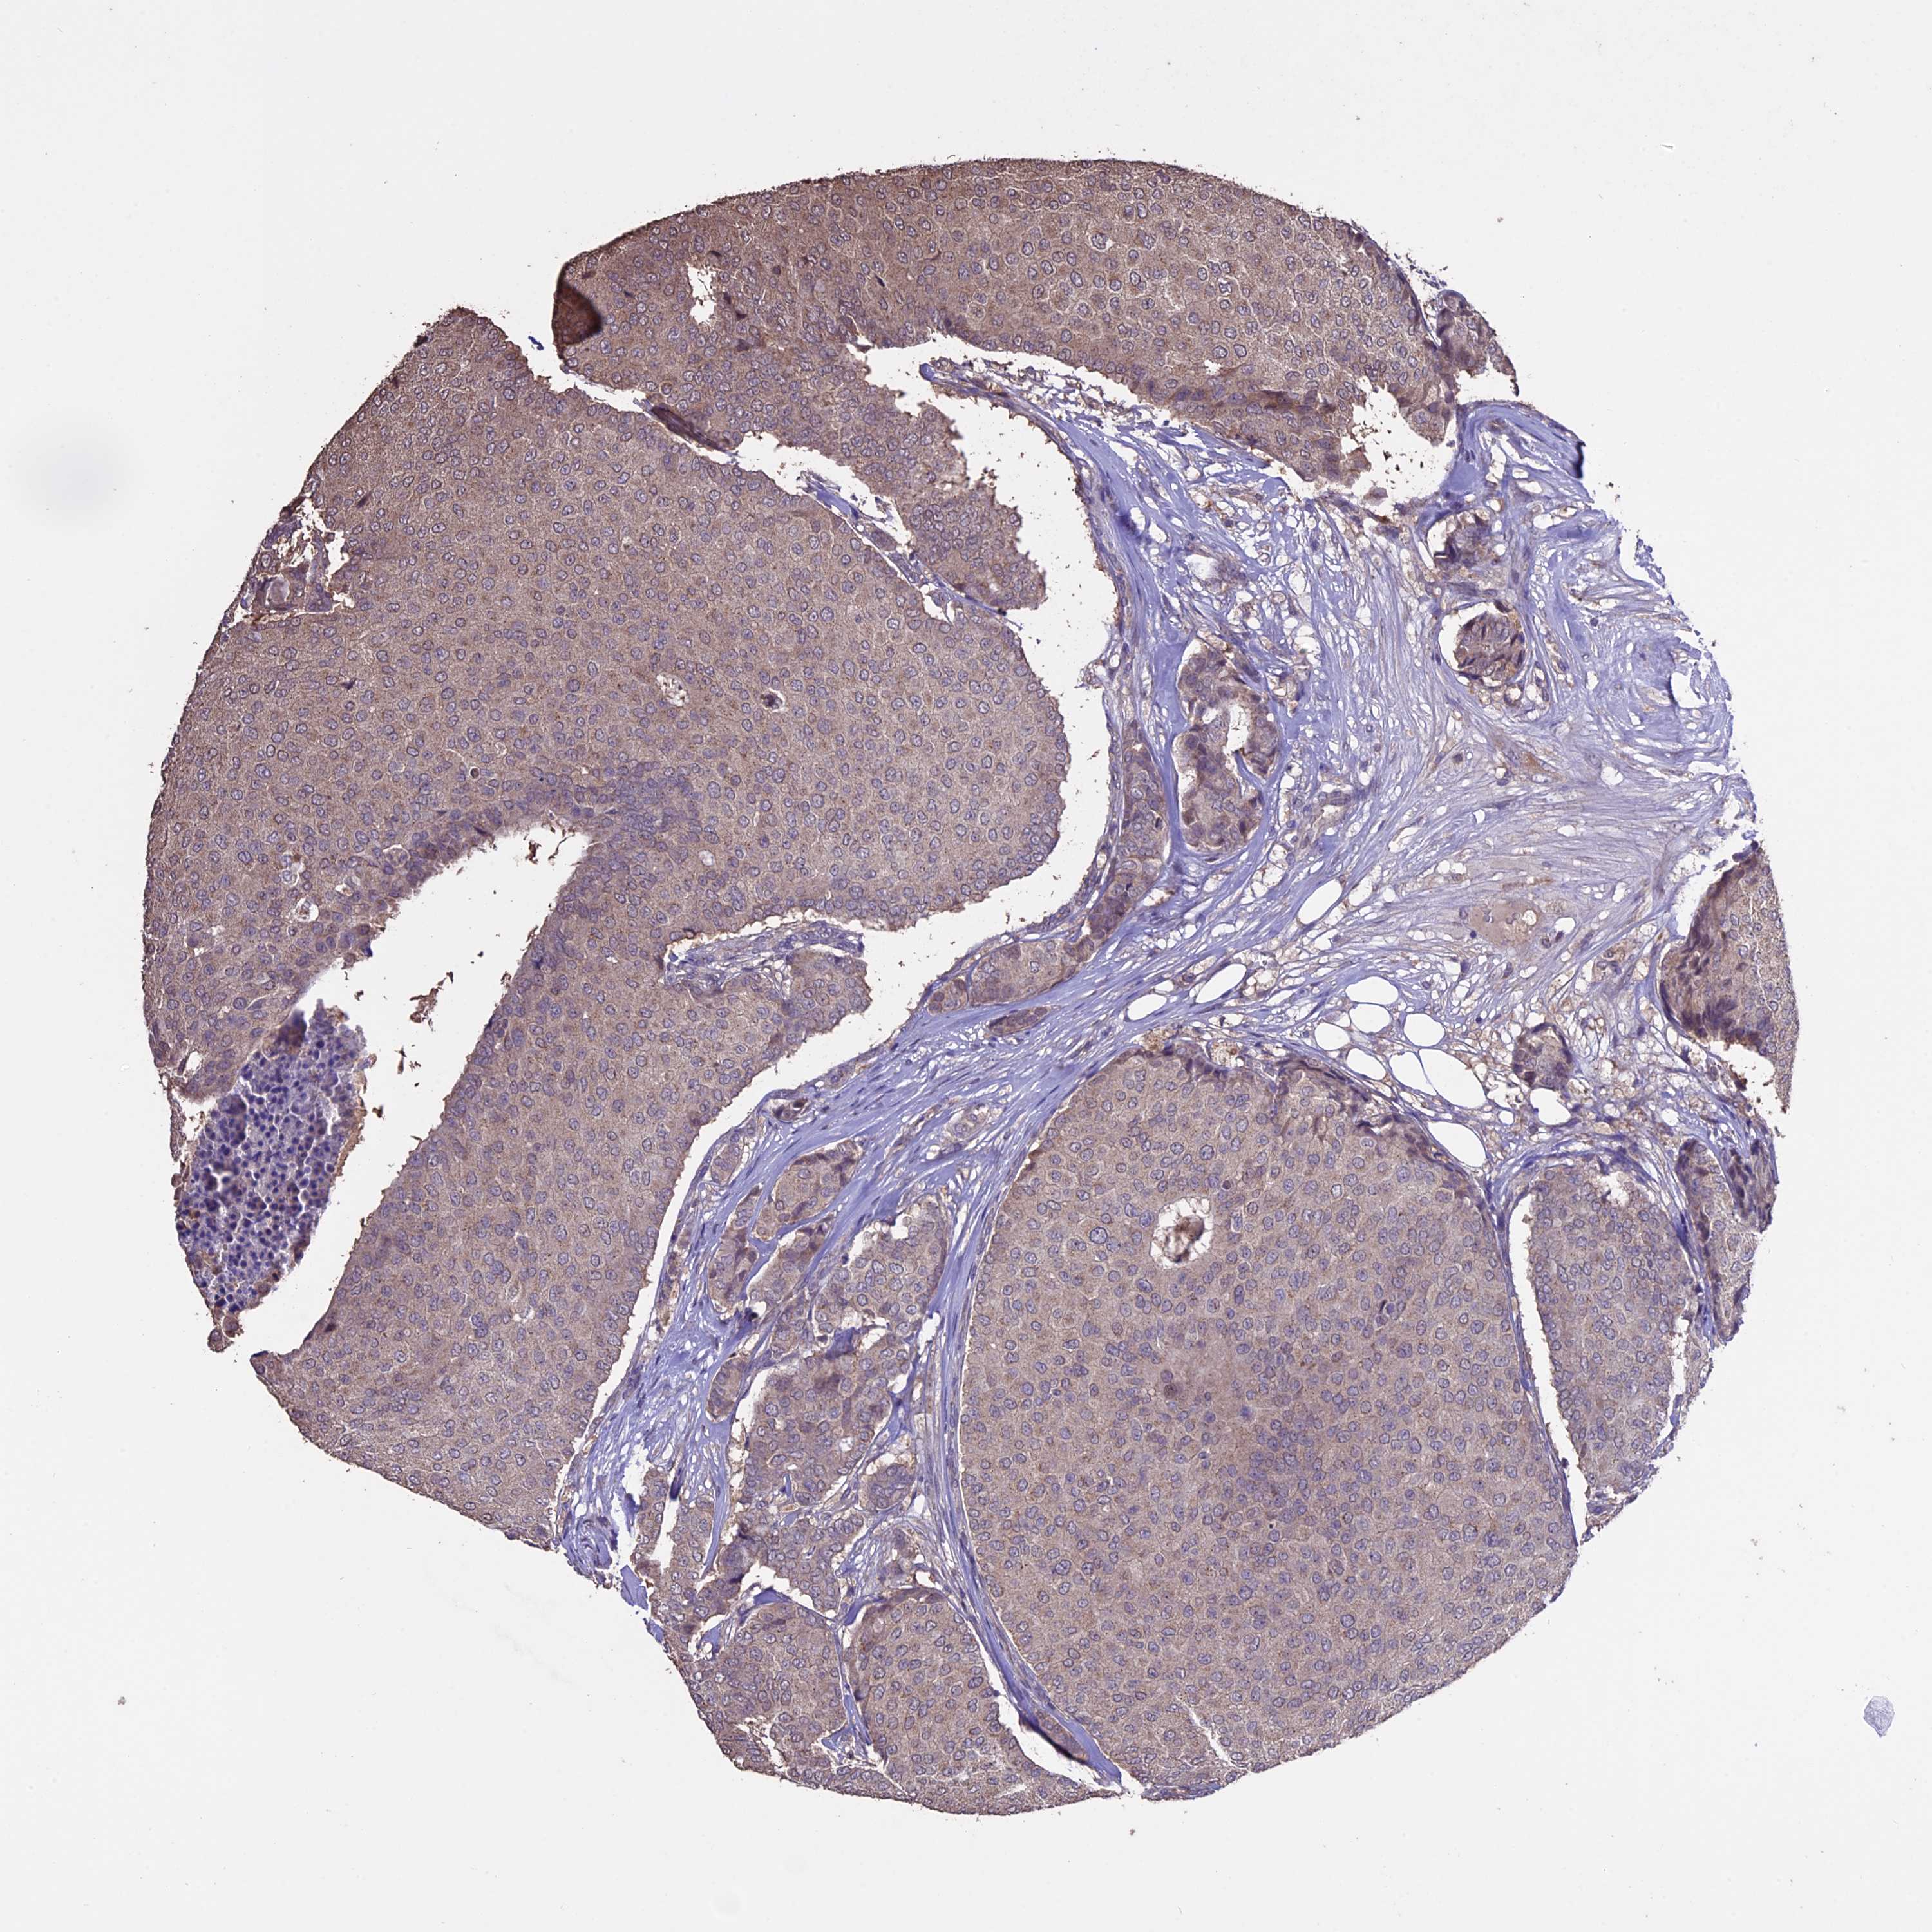

CANCER BREAST CANCER Show tissue menu

BRCA TCGA BRCA VALIDATION PROTEIN EXPRESSION